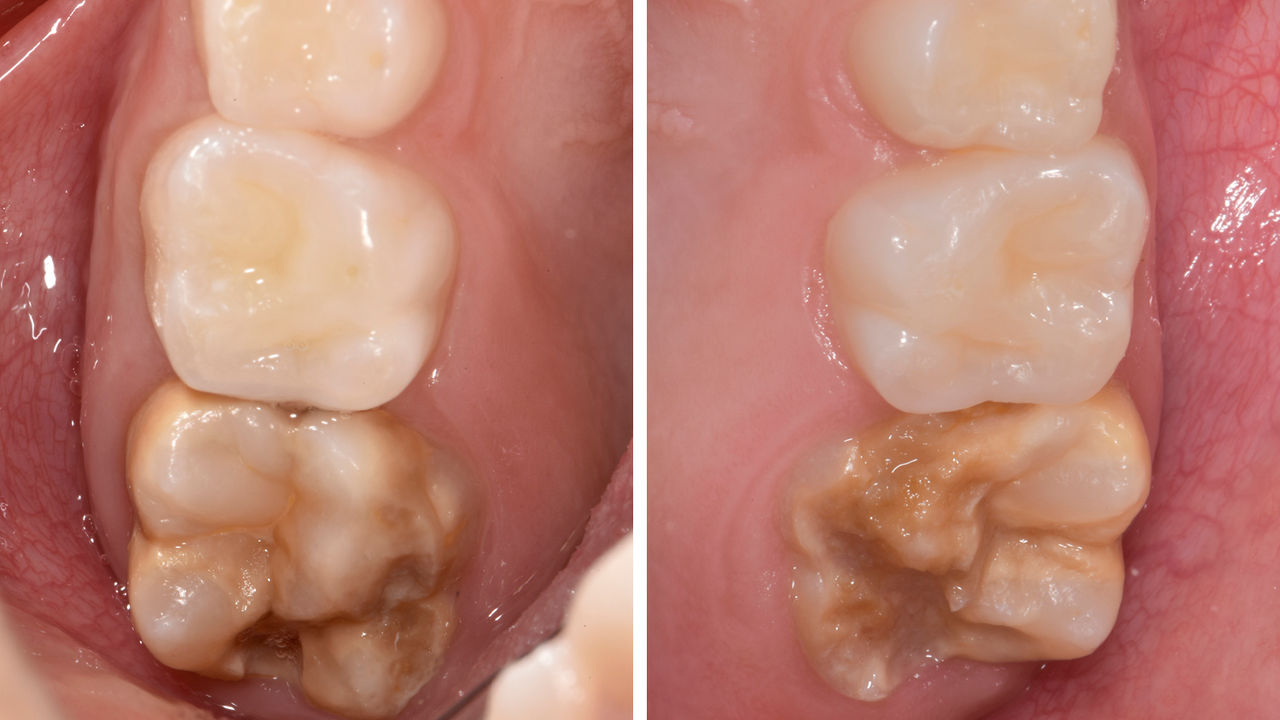

Avant : Restauration en amalgame défaillante nécessitant un remplacement. Patient se plaignant de sensibilité et dent présentant de multiples fissures.

Après : Restauration d’une couronne partielle CFAO réalisée en consultation avec la vitrocéramique CEREC Tessera Advanced Lithium-Disilicate.